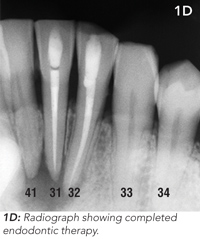

The patient underwent endodontic (root canal) therapy to the lower incisor teeth (31 and 32) and reported that the discharge ceased a week later. Photographs taken at 3-month follow-up showed resolution of the tract (Figure 1C and 1D).